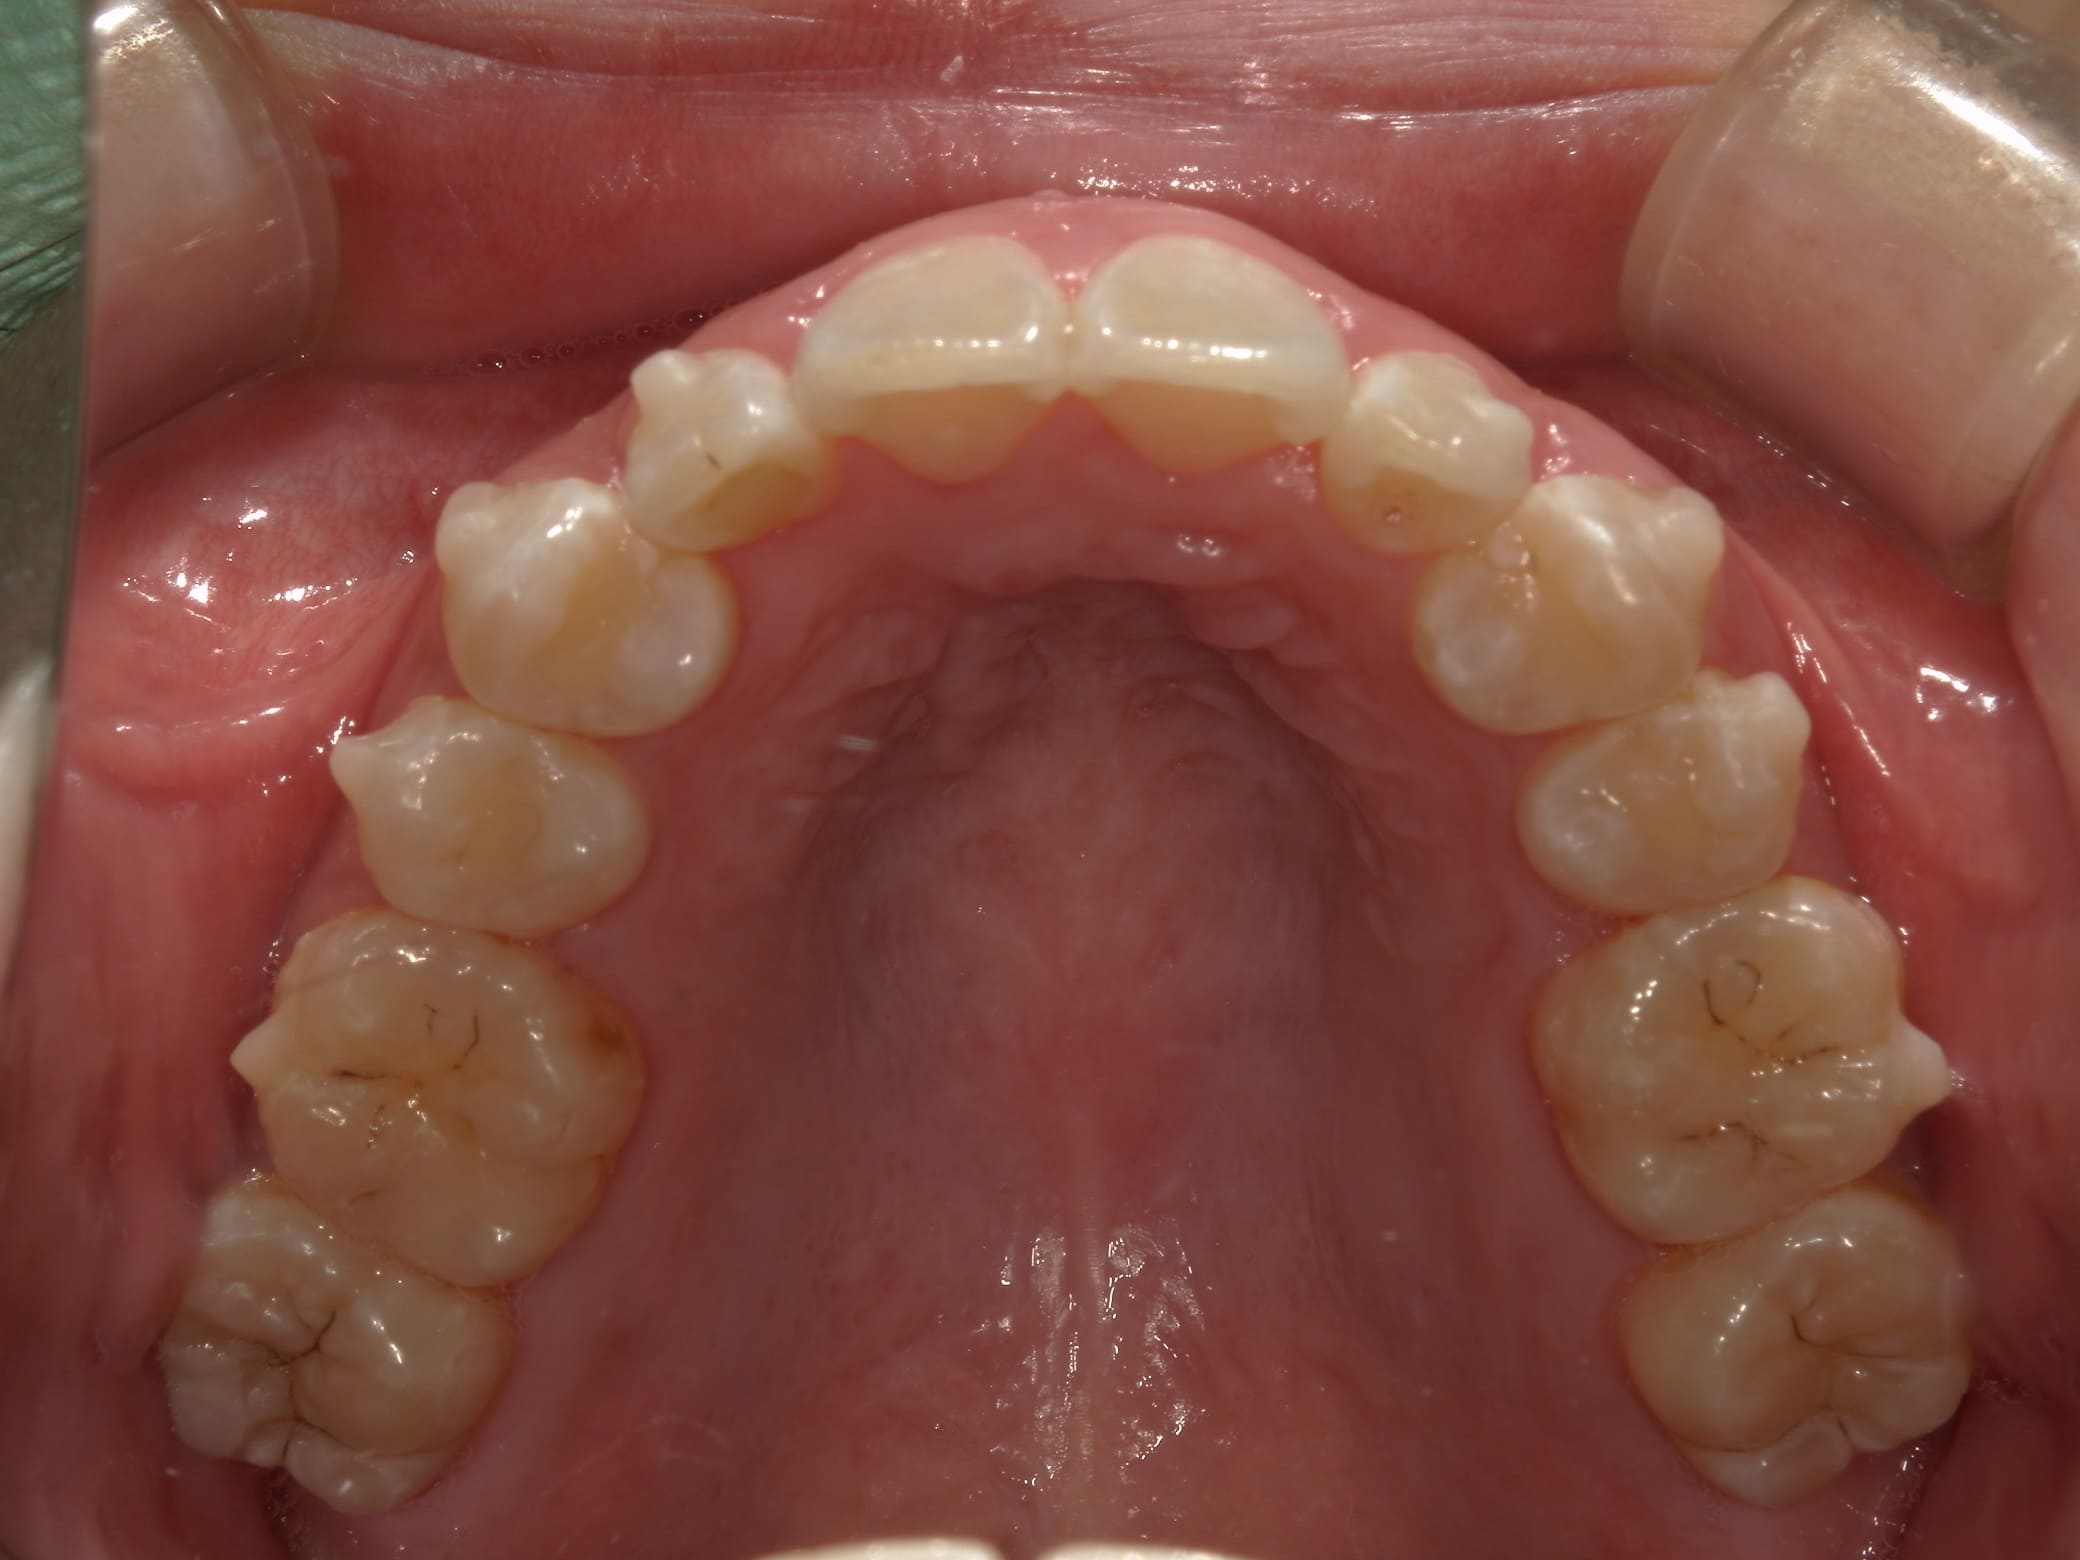

| 主訴 | 叢生が気になる |

| 治療期間・回数 | 2年 |

| 費用 | 935,000円 |